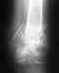

Re: Перелом пяточной кости обеих ног

Уважаемый Олег вы все же получаете лечение и вас готовят к операции ( < надеяться не накого> ). Конечно на первом этапе необходимо провести санацию инфицированных ран а уж потом операция по показаниям. Если есть какие то сомнения Вы можете обратиться ( имеете право ) за консультацией в институт. Травматологическое отд. по "свежей травме" тел.(343)3713182 зав.отд.Челноков Александр Николаевич